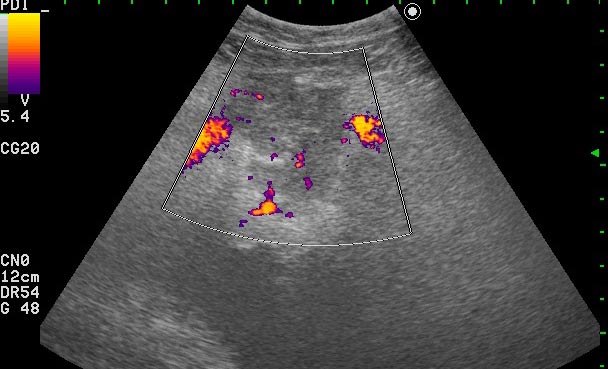

Пациентке была выполнена биопсия образования, назначена антибактериальная и противовоспалительная терапия.

Клиническое выздоровление через 2 недели. Сонограммы мочевого пузыря через 6 недель:

Если бы это было воспаление кисты, то мы бы видели изначально кисту с акустически непрозрачным содержимым. После лечения мы бы видели кисту с анэхогенным содержимым.zubr писал(а):У Митькова аналогичное образование названо воспаление кисты урахуса,что в принципе суть не меняет,а предполагает аналогичную тактику.